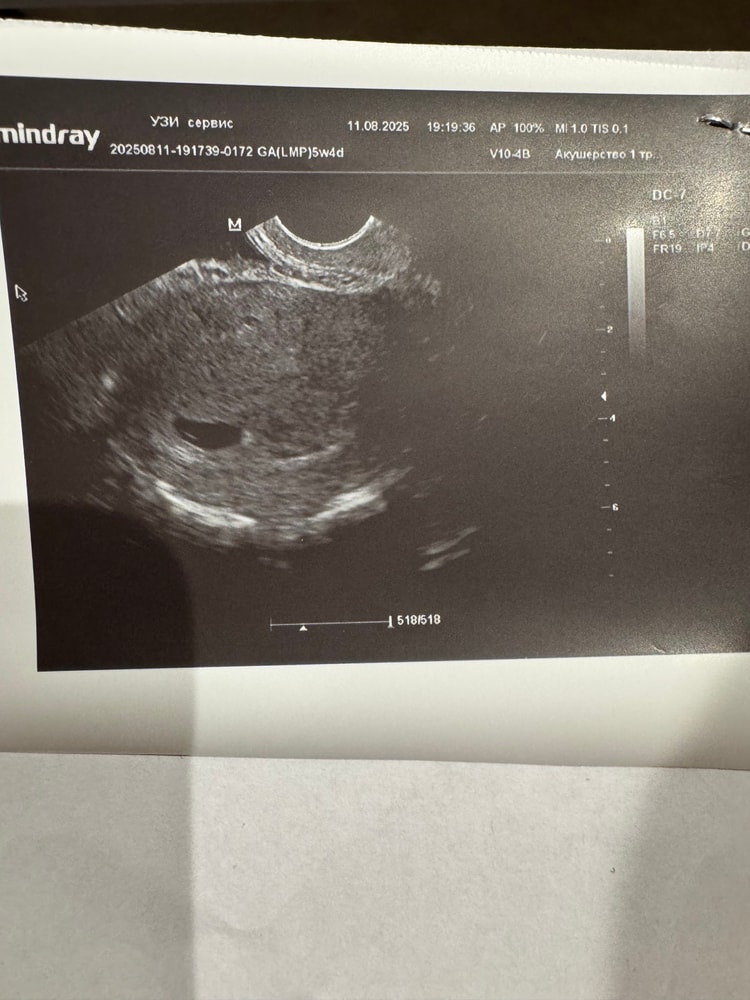

УЗИ

У нас получилось! Я беременна!Ходила 11 числа на узи, эмбриона еще нет,сказали потому что срок маленький. Но у меня какой-то страх,что вдруг у малыша так и не забьется сердечко. В первую беременность вообще даже не думала об этом.

Арина, сказал нужно будет повторить узи через 7-10 дней,к этому времени уже должен визуализироваться эмбрион и уже можно будет прослушать сердцебиение